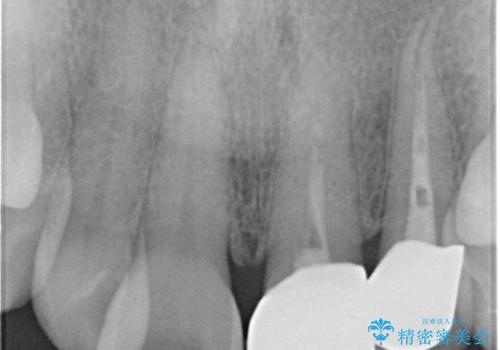

- 前歯の変色を主訴に来院された患者様です。

再根管治療からのやり直しも提案しましたが、特にご希望されなかったためクラウンでの修復処置のみ行います。

歯は根管治療が終了して時間が経つとだんだん茶色く変色していきます。